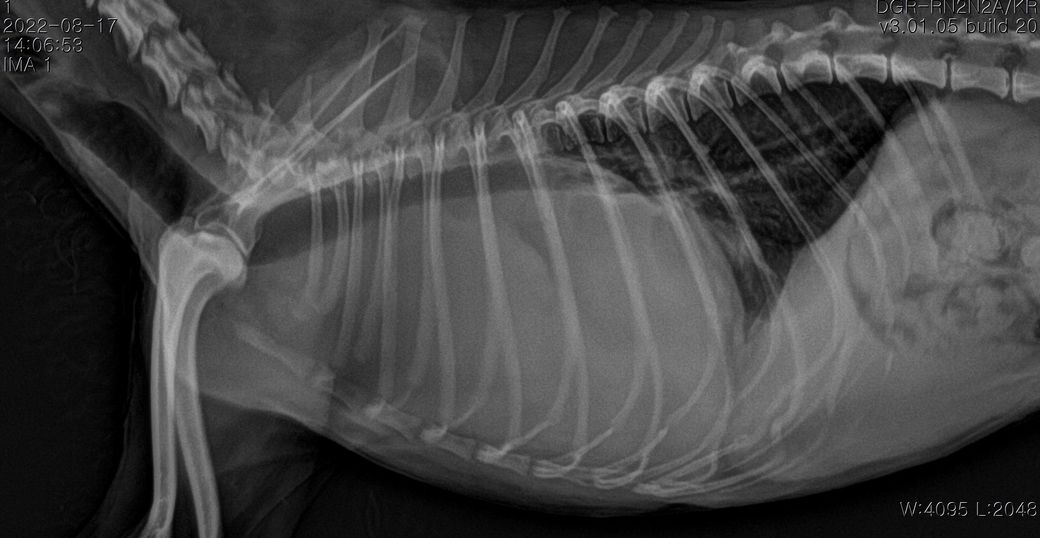

강아지 폐종양 의심되는데 봐주실 수있을까요?

폐에 종양의심소견이 보인다고 해서요.

7월부터 기침을 간헐적으로 하다가 최근 심해져서 병원에 갔는데 엑스레이 상 폐종양이 의심된다고 해서요.

첨부해주신 사진만을 기초로 볼때 폐종양인 경우 좌측 폐전엽부의 종양이, 폐종양이 아닌 경우 종격동내의 종양 특히 흉선종양의 가능성이 높아 보입니다.

이 두가지 종양의 가능성이 사실 가장 높은 상태에서 CT 촬영을 해보아야 하는 이유는

폐종양의 경우 수술로 적출하는것이 비교적 수월하고 수술 이후 어느 정도 절제 하느냐에 따라 정상 생활까지 가능한 상태가 될 수 있기 때문입니다.

물론 폐 종양이 좌측 폐 전엽의 앞쪽 부분에 국한하여 있을 때만을 이야기 하는것으로

만약 좌측 폐전엽의 뒤쪽 부분까지 적출해야 하는 상태의 종양인 경우 수술 이후 호흡 부전이 잘 오고 산소처치를 계속 받으면서 살아야 할 가능성도 고려해야 합니다.

좌측 폐는 산소 교환 능력의 40% 정도를 차지하고 폐엽 절제술 후 산소 교환능에 영향을 주는 기준점이 40% 폐엽이니까요.

또한 흉선종인 경우 이정도 크기로 증가하는 경우에는 대부분 adenocarcinoma인 경우가 많고 그런 양상인 경우 혈관이나 미주신경 침습등의 가능성이 높아 수술불가 판정이 나올 수 있습니다.

앞으로의 처치 방향을 결정하기 위해서라도 CT 촬영을 통해 수술 가능종양인지, 수술을 하지 않더라도 다른 중재적 시술이나 내과적 치료의 플랜을 짜야 하는 상황이라고 보시면됩니다.